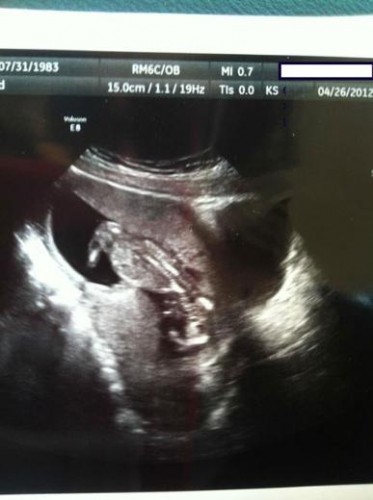

Ördek